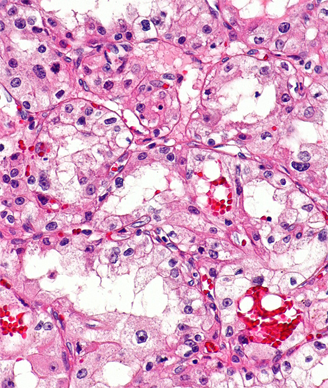

Micrograph of clear cell RCC; source: Nephron, Wikimedia Commons